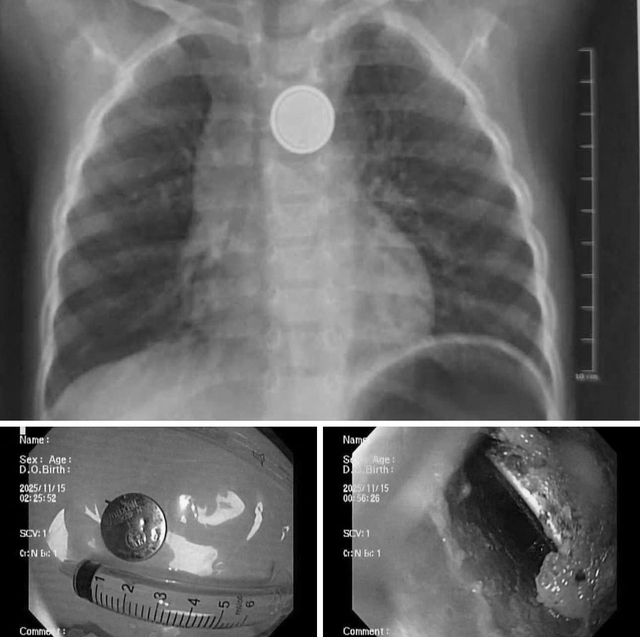

Hình ảnh dị vật là pin cúc áo trong thực quản trẻ khi được chụp X-quang và nội soi.

Tại đây, các bác sĩ đã tiến hành chụp X-quang, kết quả cho thấy dị vật kẹt tại thực quản.

Ê-kíp nội soi cấp cứu đã nhanh chóng tiến hành gắp thành công viên pin ra ngoài. Dù được cấp cứu sớm song qua quan sát trực tiếp, e-kip nội soi ghi nhận có vùng ăn mòn, gây loét thực quản.